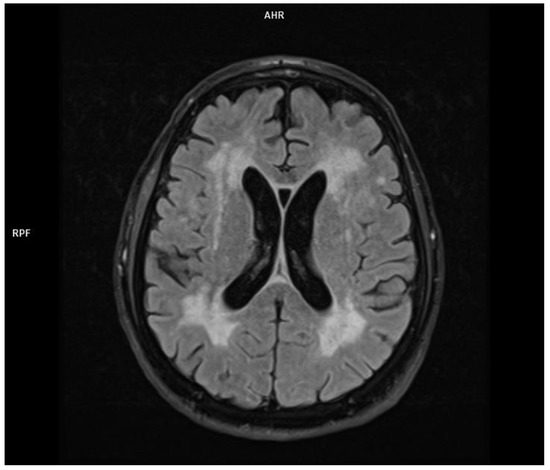

2.3. Patient 3